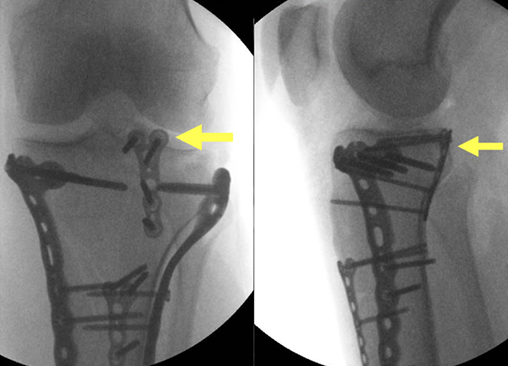

病例示例:Kfuri-Schatzker type V AL + PL + PM型双髁骨折合并后外侧“薄片型”劈裂骨折。 本例采用 Frosch入路(改良单切口双窗技术)进行处理,并应用了垂直放置的支撑钢板进行固定(箭头指示)。